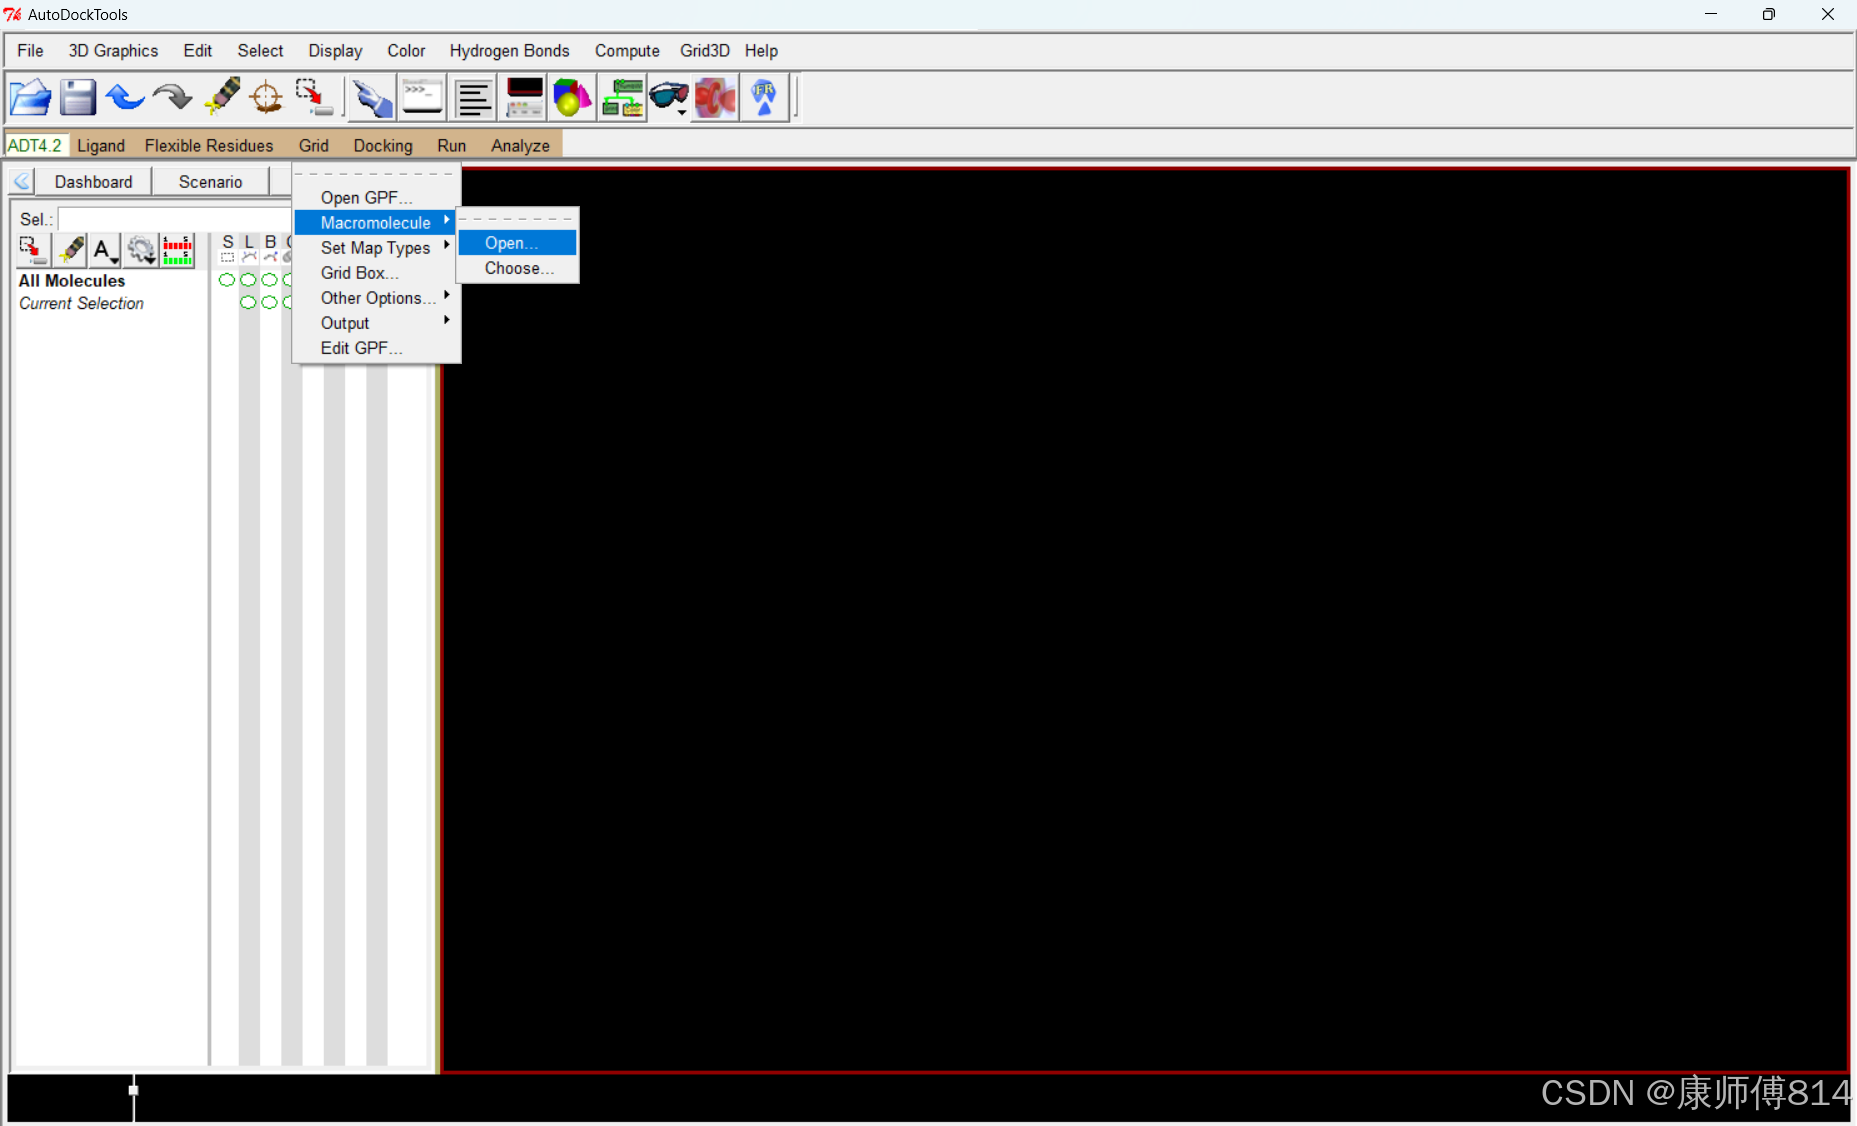

导入配体和受体文件

#点击Grid-Macromolecule-Open,选择蛋白质pdbqt文件